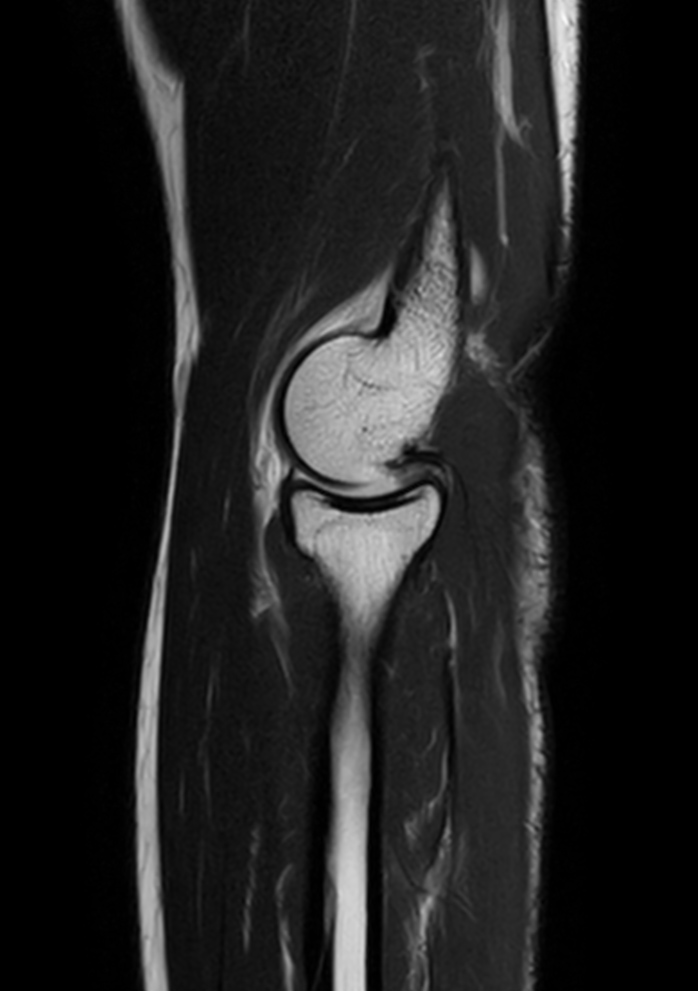

High quality Elbow imaging with Compressed SENSE

Spital Uster, Switzerland